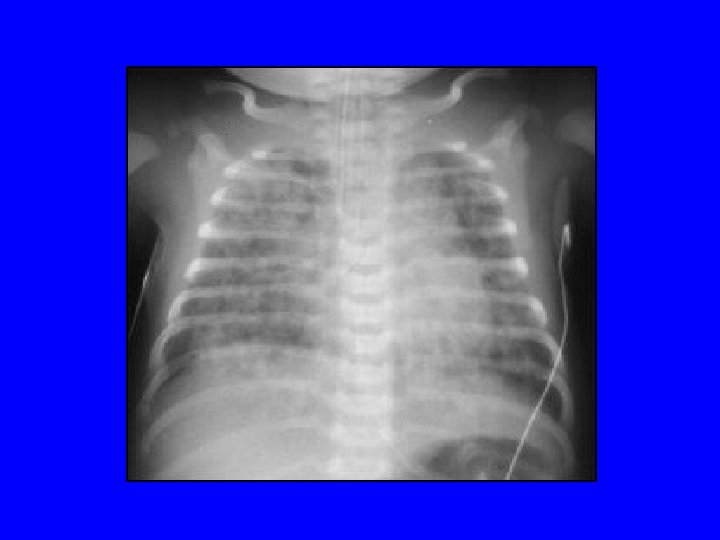

Transient Tachypnea of Newborn • It is a diagnosis of exclusion • Cause: delayed absorption of lung fluid • Risk factors: elective c/s, IDM, perinatal depression, precipitous delivery • Radiograph: Fluid in the minor fissure • Rx: supportive, resolves 2 -3 days

Case • An infant is delivered by c/s at 34 wk GA. There is no h/o ROM, maternal fever, or abn. FHR. The infant requires IPPV with a bag-mask and 100% O 2 in the delivery room. AS are 5 and 7. UA p. H was 7. 23. He is admitted to the WBN, but develops respiratory distress within an hour of life. RA ABG shows 7. 10/ 80/50/-10 with CXR